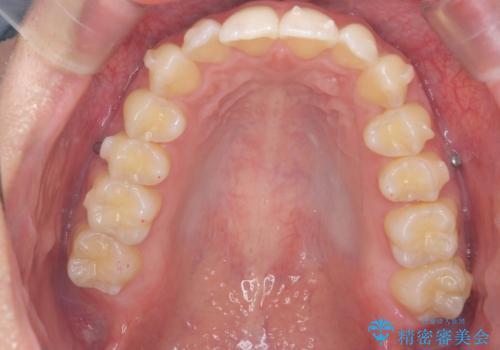

過蓋咬合・上顎前突・叢生を改善するマウスピース矯正

- 前歯のがたつき、不揃いさの改善を求めて来院されました。

・前歯の深い噛み合わせ (過蓋咬合)

・上顎前突(Angle Class2)

・叢生(がたつき)

以上のような問題点をマウスピース矯正インビザラインとマイクロインプラントを用いて矯正治療を行い改善して行きます。